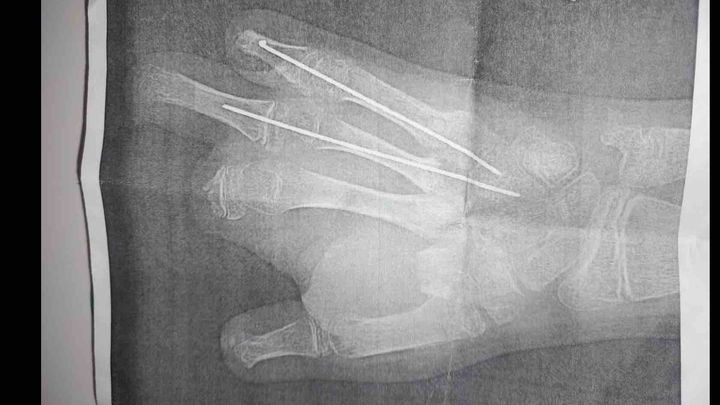

On June 23, my family’s world was turned upside down. My 12-year-old little brother was severely injured when a firework exploded in his hand. In an instant, he lost most of the fingers on his right hand—his dominant hand. The injuries were so severe that he had to be airlifted by helicopter to the hospital, where doctors rushed him into surgery.

He spent the next two weeks in the hospital, undergoing multiple surgeries in an effort to save what they could and begin the long road to recovery.